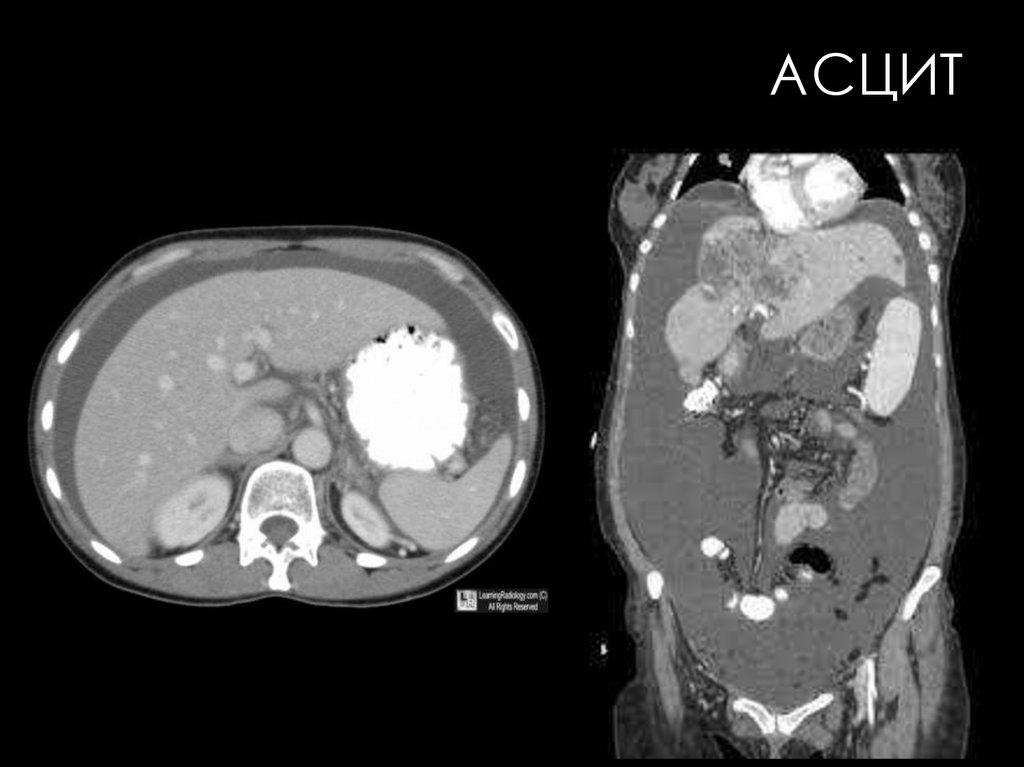

120. АСЦИТ

брюшной полости (асцит);